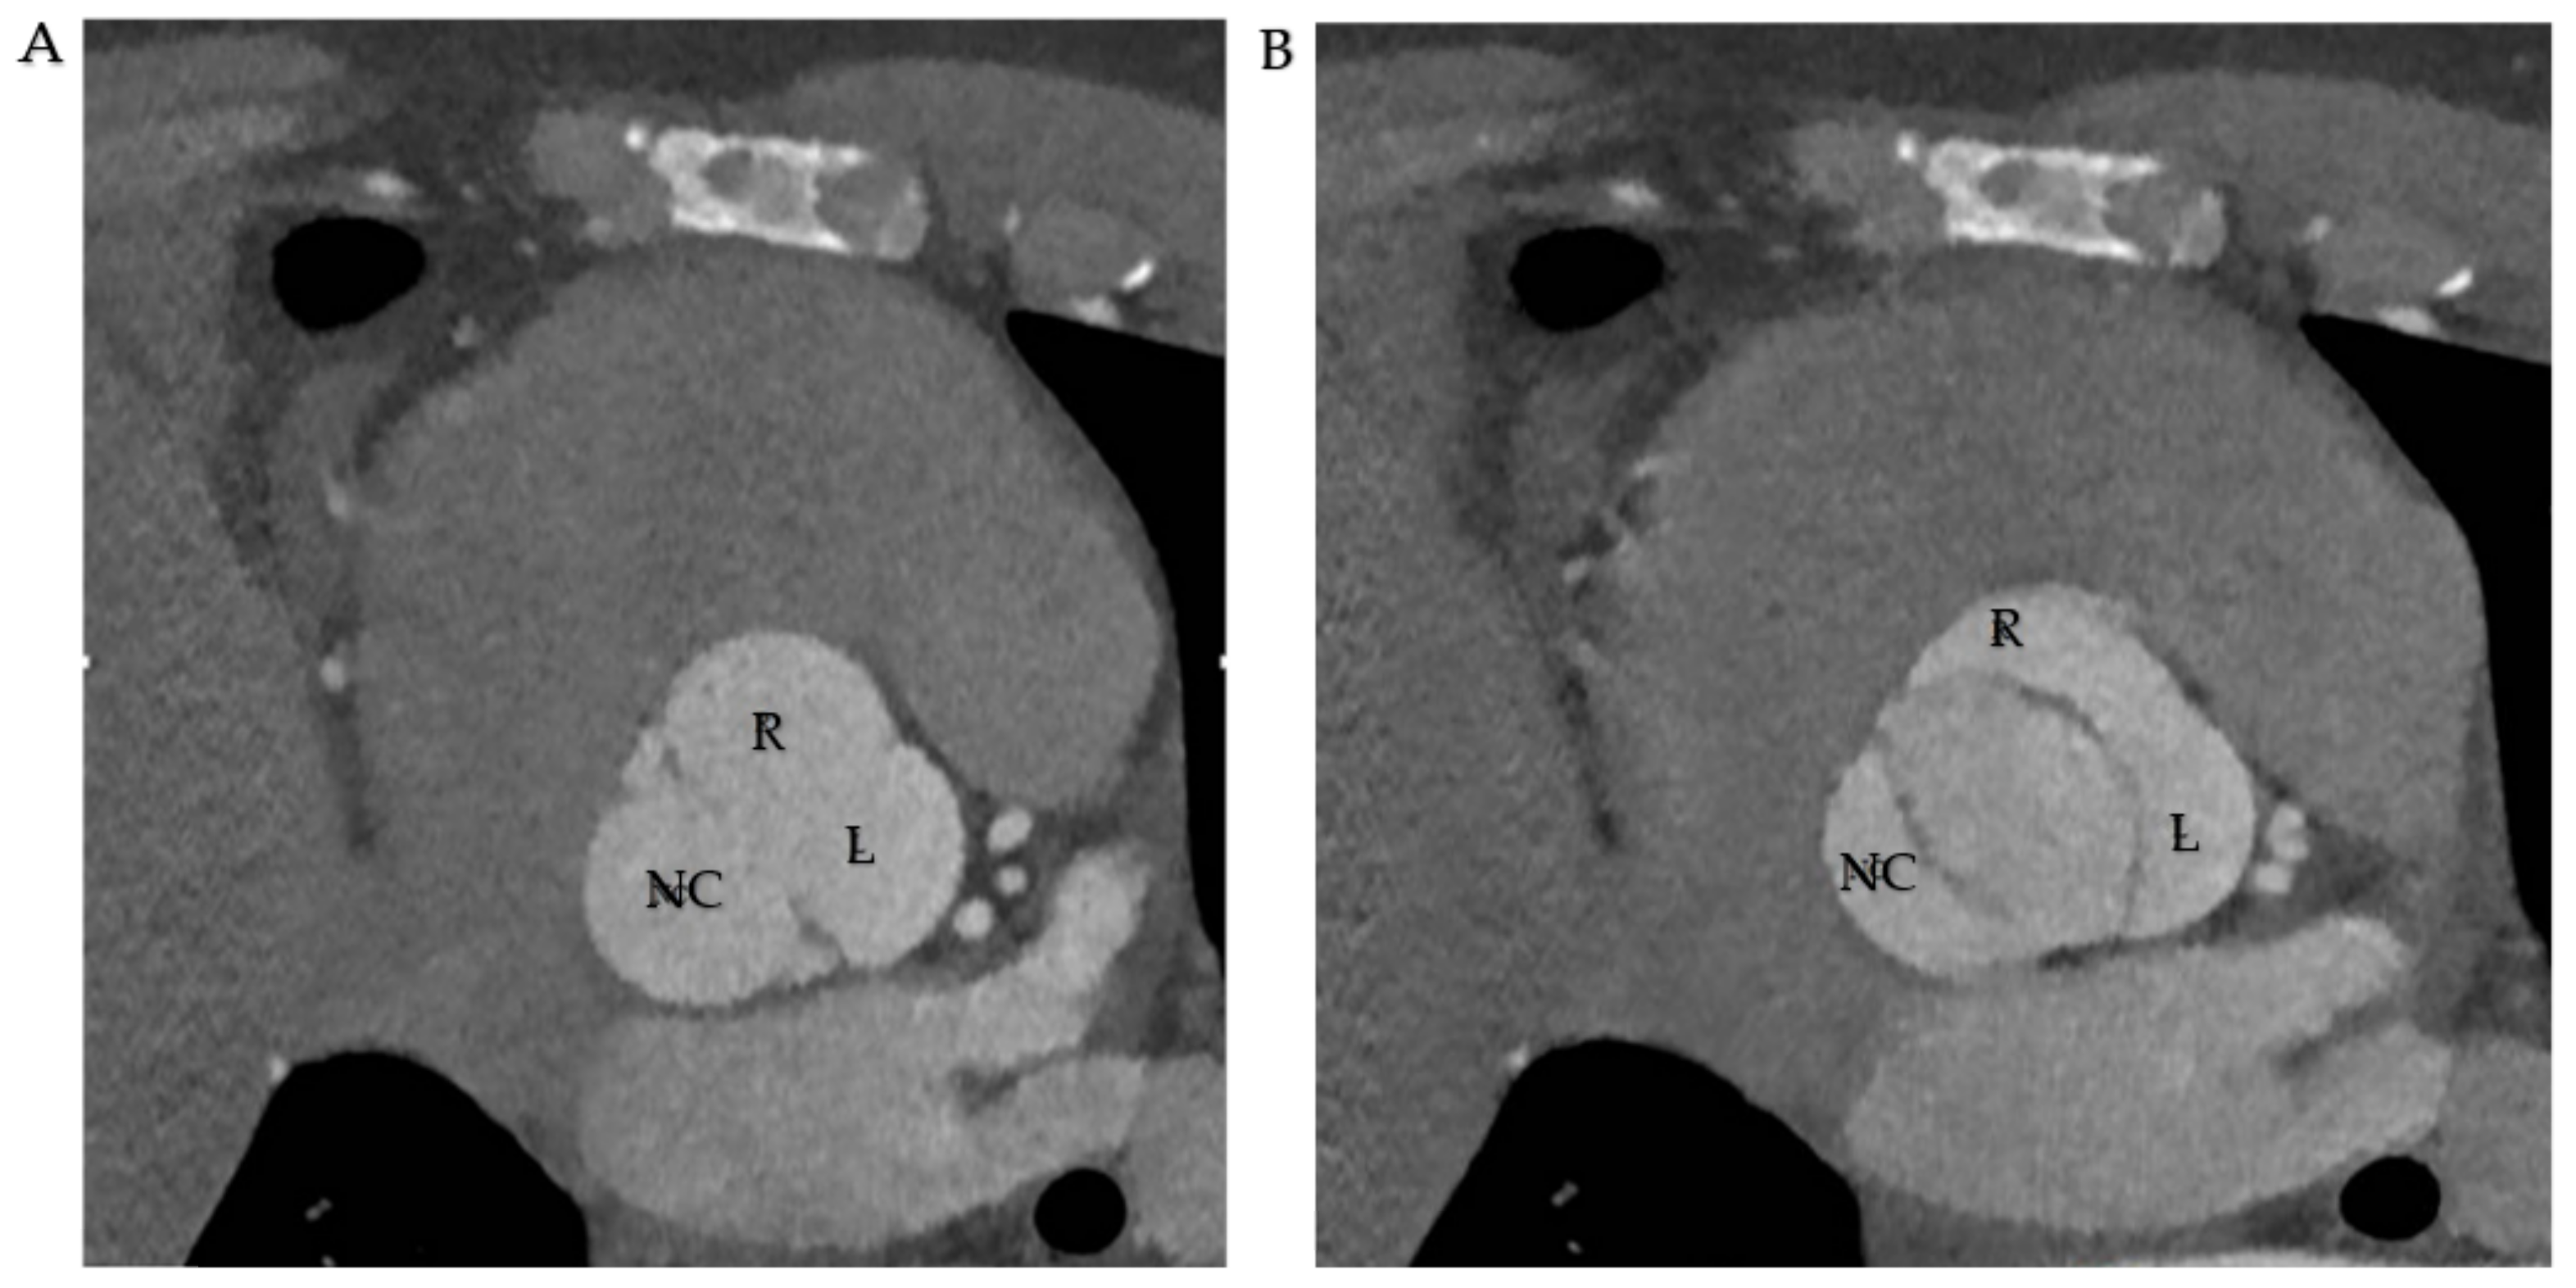

Cardiac computed tomography (CCT) complements US scans in BAV diagnosis. It is relevant in determining aortic dilation, the anatomical edges and correlation with closer structures, and discovering other pathologies correlated with BAV, such as aortic coarctation. Therefore, the radiological protocol is scheduled to determine those features useful for surgeons in the act of choosing traditional surgical approach or transcatheter aortic valve replacement (TAVR) [94] (Figure 8).

Figure 8.

(A,B). CT scan in R-L cusp fusion. (A) Three sinuses are represented. (B). Opening mechanism in fusion pattern. Abbreviations; R, right coronary cusp; L, left coronary cusp; NC, non-coronary cusp.

In order to diagnose BAV, a 64-slice CT with a venous infusion of 50–100 mL of iodine contrast medium is usually performed. It is helpful to evaluate both systolic and diastolic ECG gating phases, and in the case of BAV, a true commissure or a raphe should be determined [95]. The systolic phase shows the opening pattern of the valve and helps to register the size of the annulus and the leaflets. In the diastolic phase, the edges of the leaflets, their hinge to the aortic wall, the way they close the left ventricle outflow, and the presence of calcifications on their surfaces may be evaluated; coronaries’ imaging should also be evaluated keeping a strict monitoring of heart rate. The role of CCT in determining coronary origin in BAV deserves special mention. Eccentricity of the ostium of the right coronary artery is more frequent (> 20°) than the origin of the left coronary artery. In 95.5% of BAV patients, the obstruction of the right coronary artery is located at the border between the right cusp and the non-coronary cusp. It is also possible to assess the right and left cusps and the right and left coronary midlines. In 97% of BAV patients, the right and left cusps are slightly displaced from the commissure. In 93% of BAV patients, a displacement of less than 20° was noted between the right and left coronary cusps and between the right and left coronary arteries as centered lines [96].